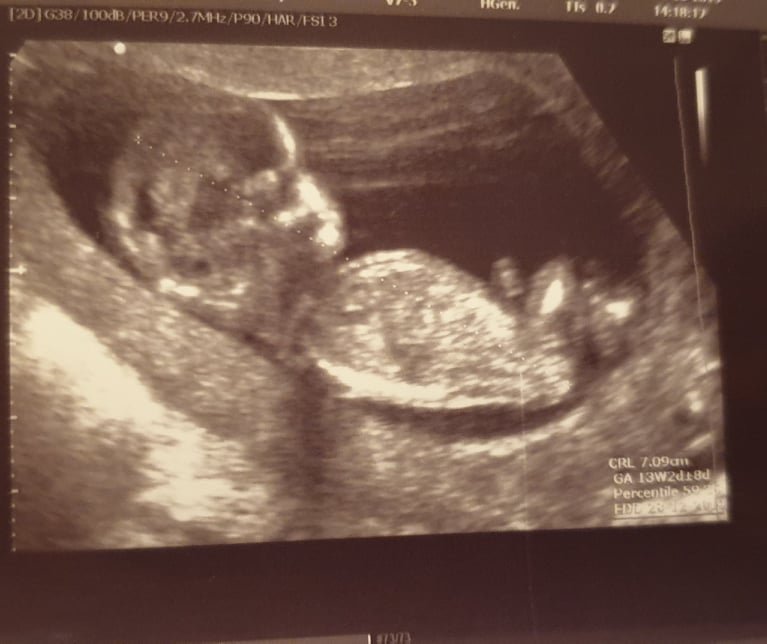

пускам снимка и аз на моето 😁 вече си се фукам с него